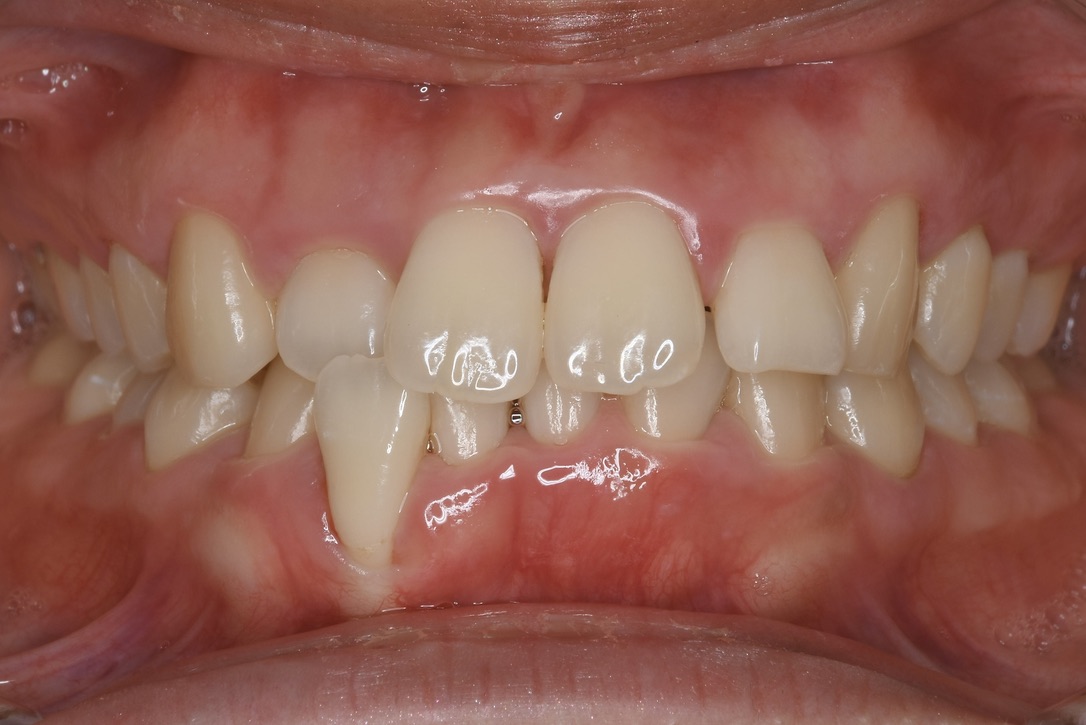

口を大きく開けて笑える、しっかり噛めておいしく食べられる、お口の中の健康を取り戻す手助けをしたい。

伊勢市の矯正歯科・くらたやま矯正歯科では、自分自身が受けたい治療、家族にも勧めたい治療をモットーに、矯正専門の歯医者としての知識・技術をもとに様々な角度から矯正治療法を提案し、患者様の悩みや希望に最大限こたえられるよう、相談しながら・寄り添いながら治療を進めてまいります。